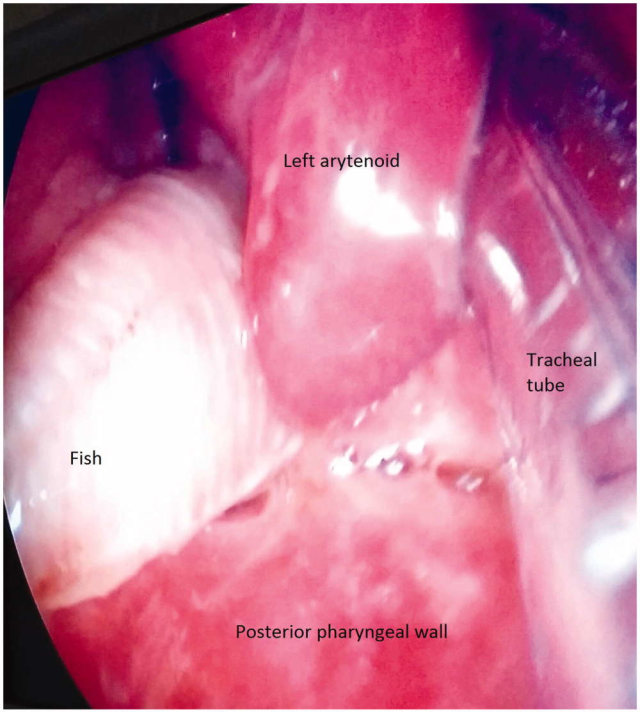

Namun, tidak dengan ikan lele beracun. Saat tahu ia dalam bahaya, ikan itu melakukan perlawanan dengan cara menusukkan duri-durinya ke tenggorakan pria yang menelannya sehingga lele itu tersangkut di tenggorokan. Beruntung, ikan itu berhasil dikeluarkan oleh tim dokter.

Kees Moeliker, kepala Natural History Museum of Rotterdam, yang memeriksa lele ini, menyatakan ikan tersebut memiliki ukuran tubuh yang kecil, hanya sekitar 5 sampai 8 centimeter. Ketika ia diserang, lele akan menggunakan durinya untuk melindungi diri dan duri tersebut bisa mengeluarkan racun.

Ikan tersebut bisa dikeluarkan melalui prosedur operasi beserta sisa-sisa dari ikan yang sudah mati di dalam tenggorokan tersebut, kemudian dijadikan koleksi di Natural History Museum of Rotterdam.